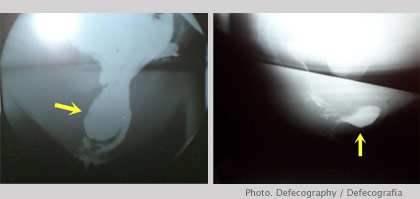

Defecography

Dynamic method of obtaining images in real time during defecation.

In combination with Magnetic Resonance Imaging MRI it enables us to detect multiple pelvic floor disorders (rectal prolapse, uterine prolapse, enterocele, cystocele, etc).